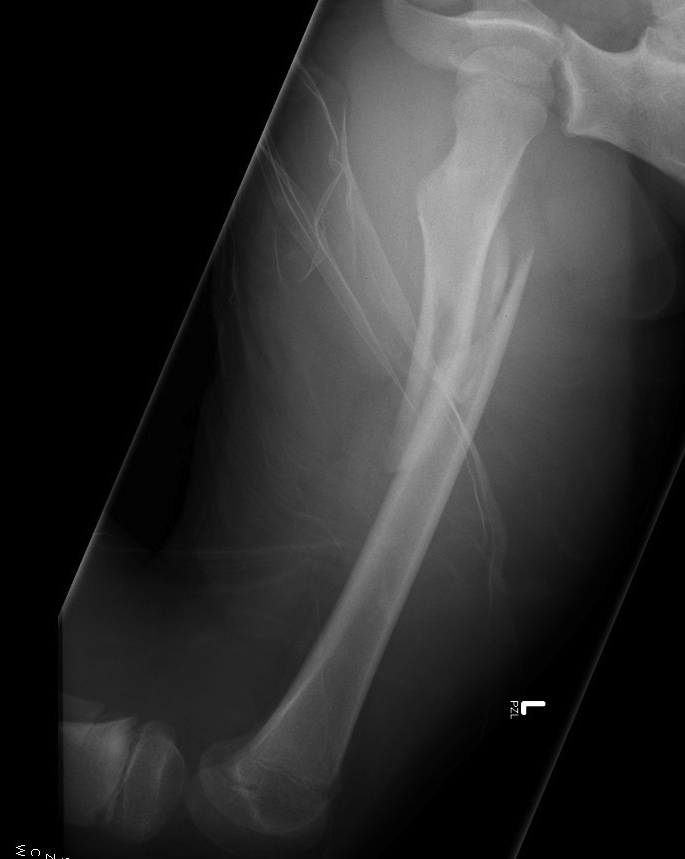

Flexible nails / Titantium Elastic Nails

Indications

- length stable i.e simple transverse, short oblique, midshaft

- maximum weight up to 50 kg / 12 years old

Contra-indications

- unstable fracture patterns

- > 50 kg

Technique

Wires

- 30 - 40% of diameter of diaphyseal medullary canal

- i.e. if canal 10 mm wide, use 2 x 4 mm

Entry points

- medial and lateral insertion

- 1 - 2 cm proximal to distal femoral physis

Wire passage

- bend wire for 3 point fixation

- also bend the tip of the wire

- medial entry wire will pass into femoral neck

- lateral entry wire will pass into greater trochanter

Acceptable alignment

- 10o varus / valgus

- 15o flexion / extension

- 15 mm shortening